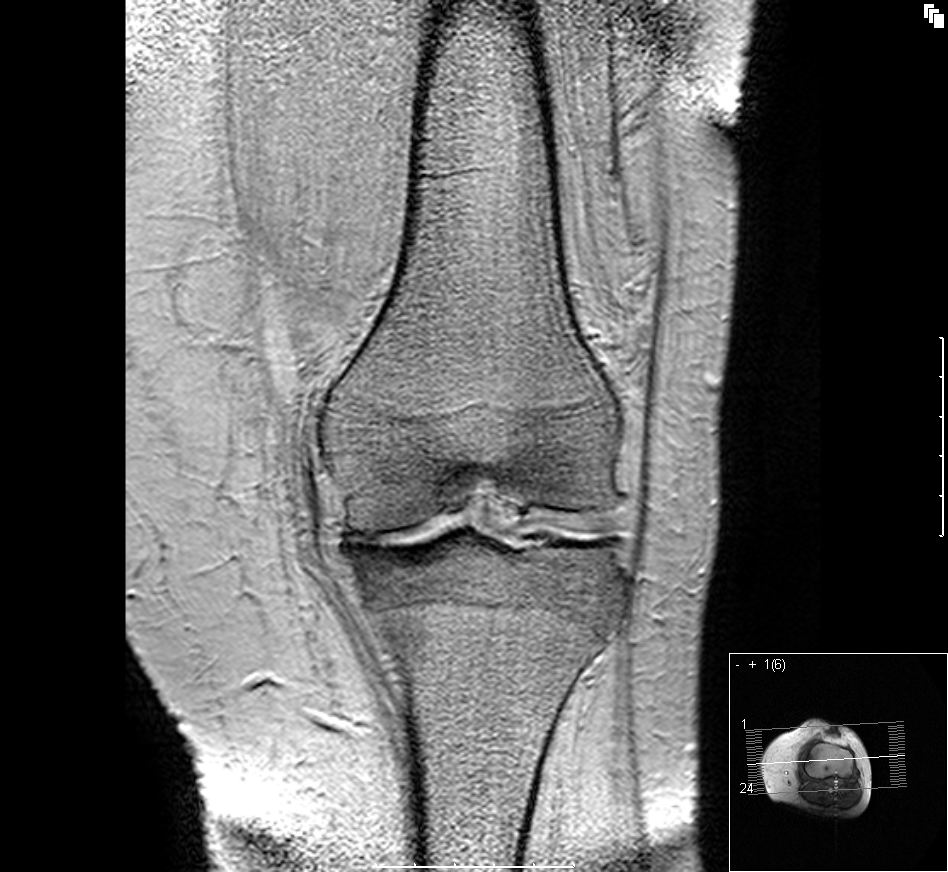

Przyczyna 3: Choroba zwyrodnieniowa stawów

Jest często związana z procesami starzenia zachodzącymi w stawach. Jednym z jej objawów są właśnie opuchnięte stopy jak i również ból w okolicy dotkniętego stawu.